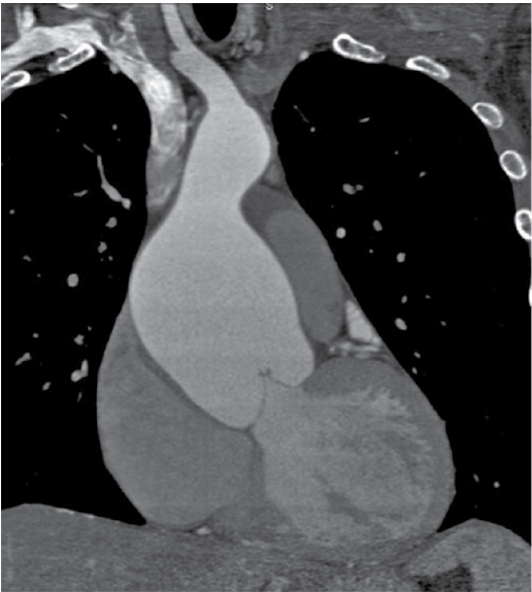

Homem, de 35 anos, apresenta quadro de dor nas costas sendo submetido ao exame mostrado a seguir.

Enunciado 3194801-1

Nesse sentido, é correto afirmar que